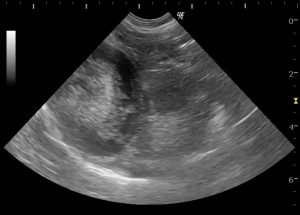

健康な子の胆嚢の超音波画像です。中心の黒く抜けている部分が胆嚢内の胆汁で、その下の暗めの灰色の部分は胆泥です。健康な子でも少しくらいの胆泥があることはよくあります。